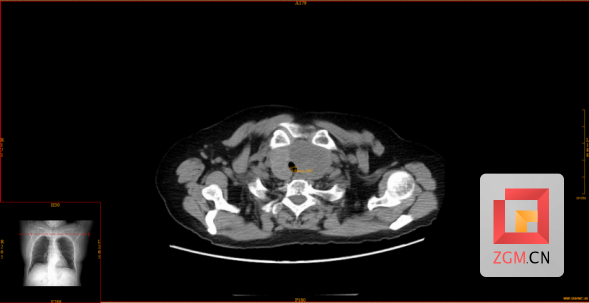

今年71岁的刘阿姨,因“摔伤致踝关节疼痛”被送到市四医院骨科中心救治。住院期间,患者突发气道梗阻,随即出现呼吸、心跳骤停。经过多学科团队的紧急抢救,患者的生命体征和意识已经恢复。随后进行的影像学检查揭示病因:甲状腺左叶存在一巨大肿物,大小约6.4×5.56×4.13cm,气管受压变窄,最窄处仅约0.588cm,已处于窒息高危状态。